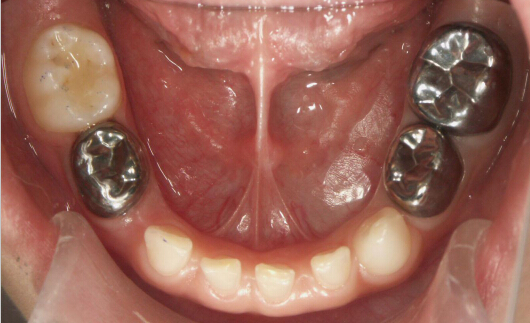

◆一般的蛀牙都能通过修补很好的解决,如果牙齿龋坏过于严重,牙洞深又大,做完根管治疗后,只是补牙就不太适用了,而需要做乳牙的预成冠。

◆乳牙金属预成冠跟恒牙烤瓷冠修复一样,一般用于乳牙做完根管治疗以后。许多家长不理解做牙冠的意义,它可以将整颗治疗后牙齿保护起来,阻断外界刺激,防止再次长蛀牙和补料的脱落,另一方面,恢复患牙完整性和外观。